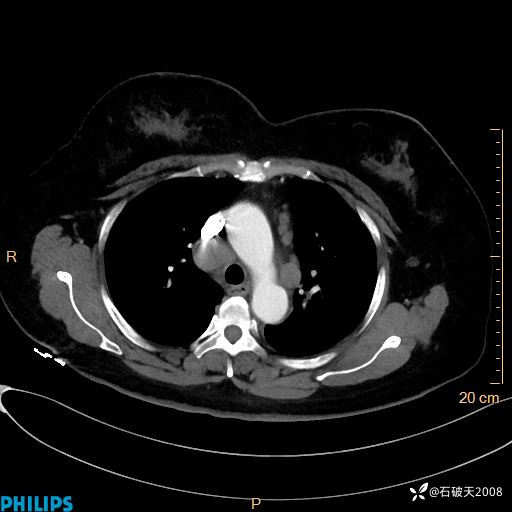

肺结节病?纵膈型肺癌?淋巴瘤?有点意思,欢迎围观

女 52岁 主 诉:咳嗽10余天,咳痰2天。

现病史:10余天前无明显诱因出现咳嗽,呈阵发性干咳,伴咽喉部发痒,无咽痛,无咳痰,无鼻塞、流涕、打喷嚏,无发热、畏寒、寒颤,无头痛、头晕,无胸闷、胸痛,无反酸、烧心,无腹痛、腹泻,无尿频、尿急,无皮疹等,在当地诊所求治,给予口服药物治疗(具体不详),病情无好转。遂在当地社区卫生服务中心开具口服药物治疗(具体不详),疗效欠佳。2天前出现咳痰,在我院门诊求治,行胸部CT提示肺部感染,建议住院,患者要求口服药物治疗,目前仍咳嗽、咳白色粘痰,白天量多,夜间自觉喉部喘鸣音,遂再次来院就诊,以“肺部感染”为诊断收入院。发病以来,神志清,精神可,饮食可,夜间睡眠差,大小便正常,近期体重无明显变化。

静脉期